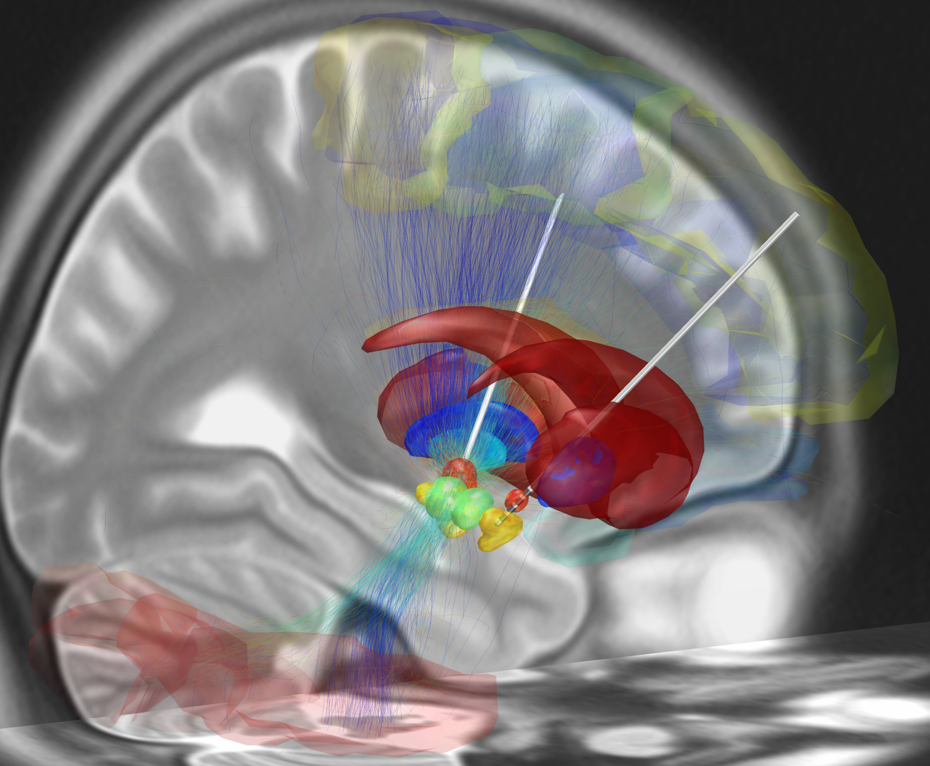

Parkinsonak begietan duen eragina ikertu du Juan Duran Oftalmologiako Institutu Kliniko Kirurgikoko zuzendari mediko eta oftalmologoak. Parkinsona gaixotasun neurodegeneratibo kroniko bat da, eta gorputzeko beste sistema batzuei ere eragin diezaieke, besteak beste, ikusmen sistemari. Duranek azaldu duenez, begiak burmuinaren luzapen bat dira, eta hainbat arazo neurologiko antzeman daitezke hauei erreparatuta. Parkinsona duten pertsonak adibidez, begiak gutxiago kliskatzen dituzte, eta gutxiago mugitzen dituzte. Datuak Berrian.

Normalean, garun-azala hizkuntzarekin lotzen dugu. Hala ere, egitura subkortikal batzuk oso garrantzitsuak dira, baina ez hain ezagunak. Subcortical nuclei and language processing, Elissa-Marie Cocquyt & Adrià Rofes.